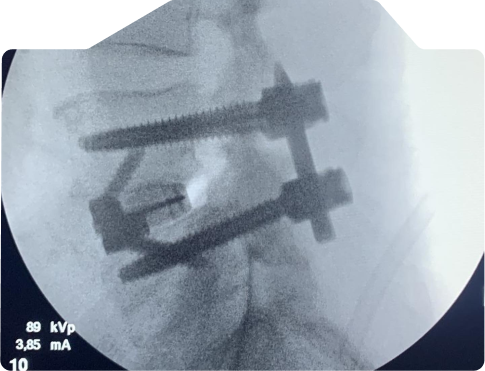

Veja casos de antes e depois dos meus pacientes:

A artrodese, também conhecida como fusão espinhal, é um procedimento cirúrgico que visa aliviar a dor. é feito a fusão de duas ou mais vértebras para estabilizar a coluna e aliviar a dor causada pelo movimento vertebral.

Após cerca de 2 horas da cirurgia o paciente pode acordar, levantar-se, comer e andar. Não é necessário permanecer deitado ou em repouso absoluto; a caminhada é encorajada.